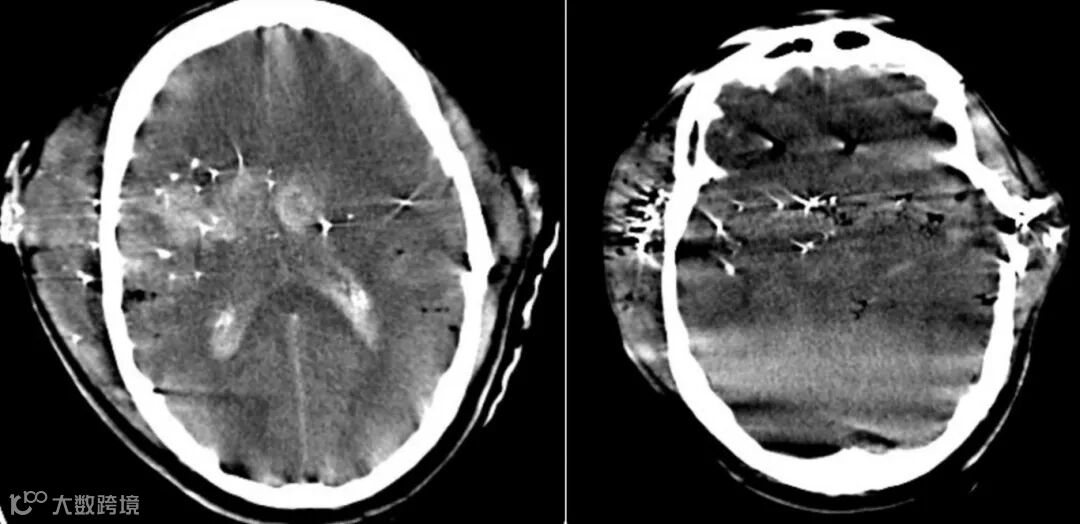

男,30岁,子弹从右向左移动,伴有颅骨骨折、脑挫、裂伤,脑内气肿、脑室积血、弥漫性脑水肿及多发弹片残留。

女,40岁,几年前面部曾遭猎枪击中,之后昏迷了5个月,近期头痛加剧。头颅CT示霰弹枪子弹主要位于脑表层。一些子弹穿透了颅骨,位于左额叶、左视神经管附近和右尾状头部。

男,77岁,复发性头痛。33年前头部曾遭受非致命性枪击。CT见穿过两个半球的弹道轨迹、神经胶质增生和多个子弹碎片。